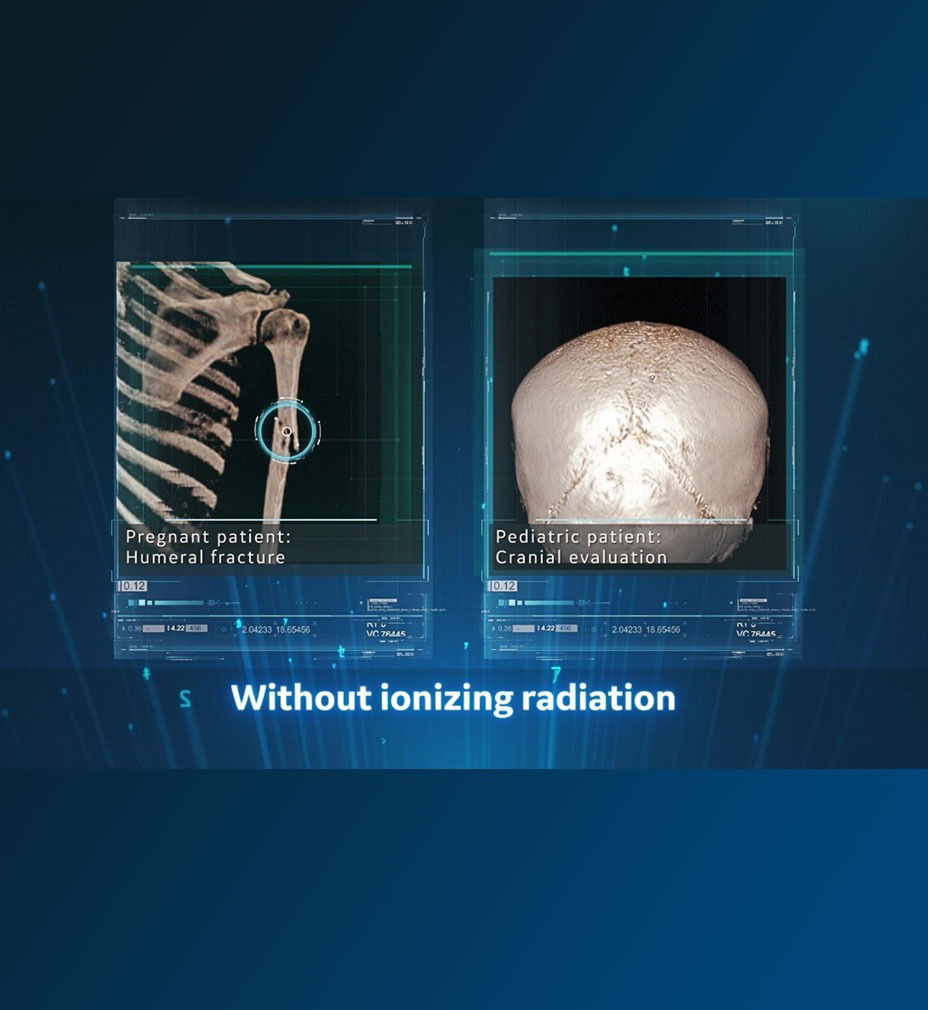

Without ionizing radiation, offers an alternative for pediatric and pregnant patients